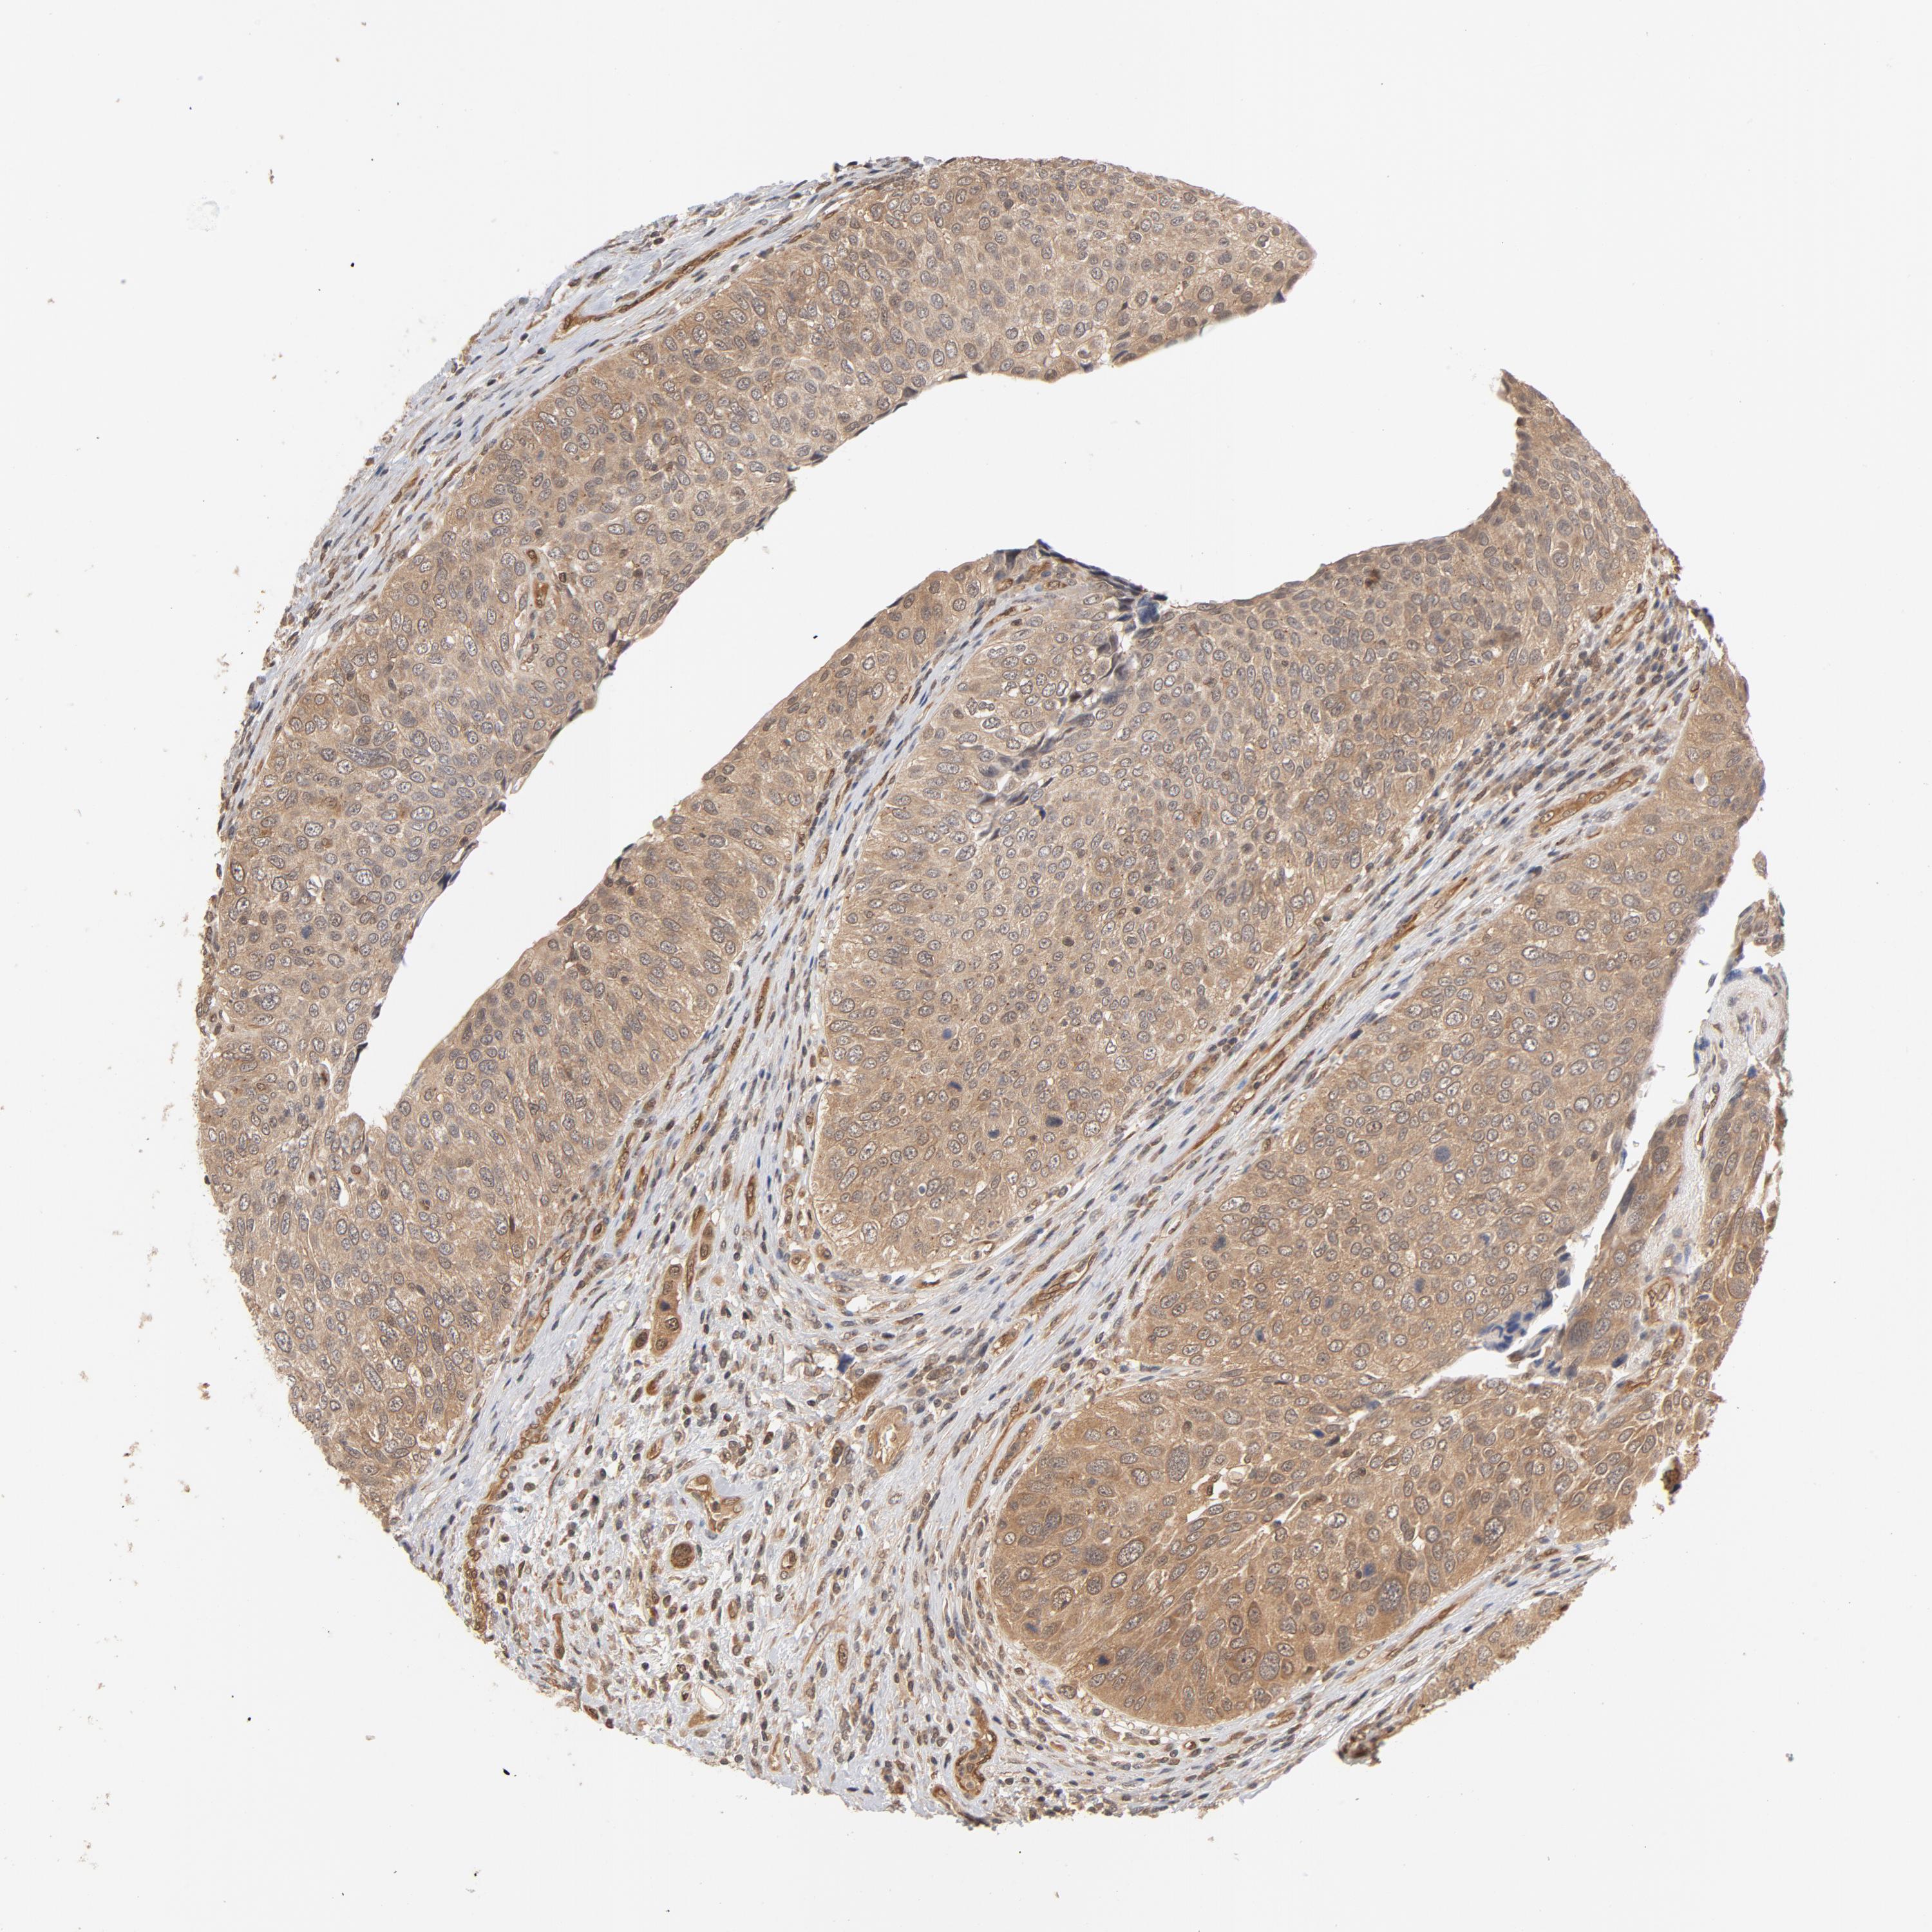

UROTHELIAL CANCER - Protein expressioni

A mouse-over function shows sample information and annotation data. Click on an image to view it in a full screen mode. Samples can be filtered based on level of antibody staining by selecting one or several of the following categories: high, medium, low and not detected. The assay and annotation is described here.

Note that samples used for immunohistochemistry by the Human Protein Atlas do not correspond to samples in the TCGA dataset.

Antibody stainingi

Antibody staining in the annotated cell types in the current human tissue is reported as not detected, low, medium, or high, based on conventional immunohistochemistry profiling in selected tissues. This score is based on the combination of the staining intensity and fraction of stained cells.

Each image is clickable and will lead to virtual microscopy that enables deeper exploration of all samples and also displays staining intensity scores, fraction scores and subcellular localization as well as patient and tissue information for each sample.

Antibody HPA003928

Antibody CAB004214

Urothelial carcinoma, High grade

Urothelial carcinoma, Low grade